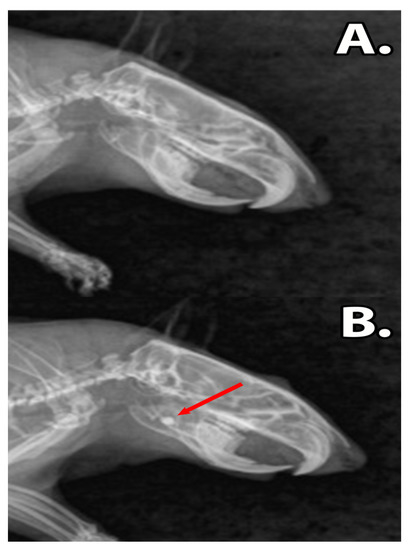

Figure 4.

The X-ray images of the rat mandibles, (A) sham surgery group. The untreated defect is too small to be clearly observed. (B) Group filled with dental restoration material. The composites are clearly differentiated due to the radio opaque properties of the material (red arrow).

Following graphene dental material implantation, the rats did not present symptoms of acute toxicity or local inflammation. The ingestion of solid foods was restarted after 12 h post-surgery and the body mass of the rats remained unaffected (p > 0.05) (Table 2). The X-rays revealed that the dental materials, GZ2 and LC1, were present in the bone defect during the experimental period, without any signs of resorption or disintegration of materials (Figure 4).